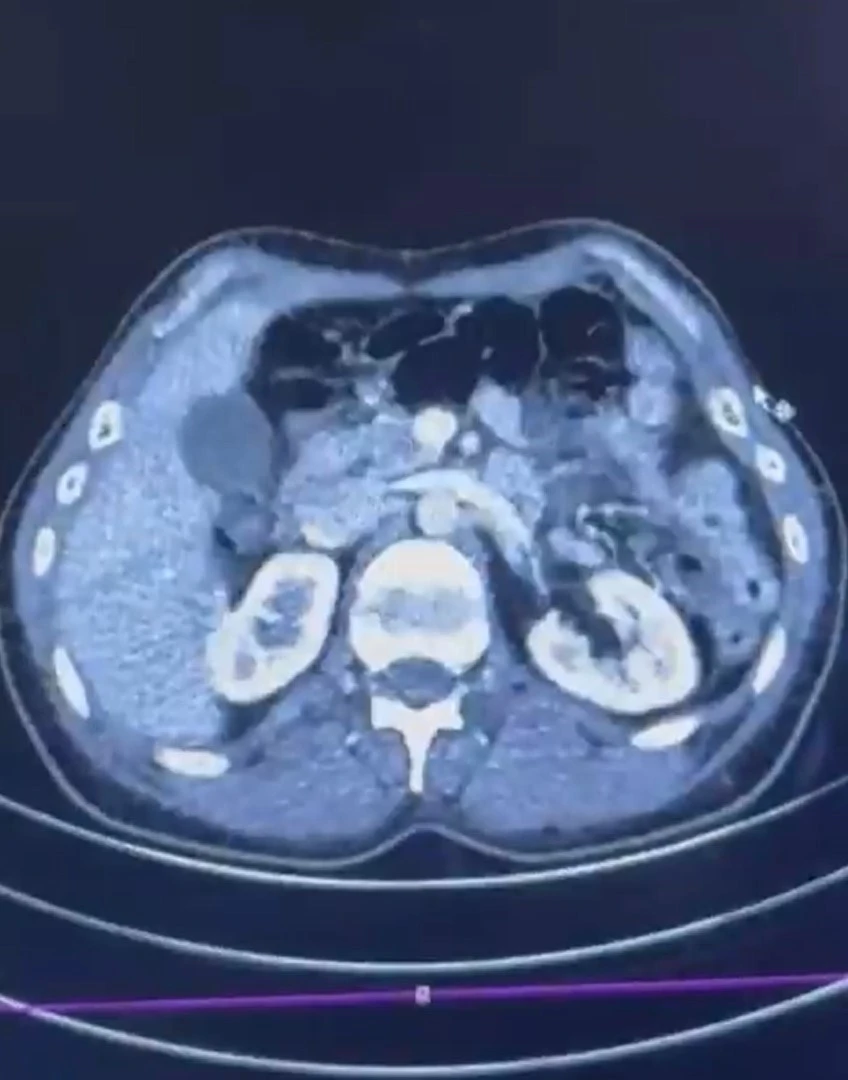

Kayseri İl Emniyet Müdürlüğü Narkotik Suçlarla Mücadele Şube Müdürlüğü ekipleri, uluslararası uyuşturucu ticaretine yönelik çalışmada İran'dan Türkiye'ye gelen 3 şüpheliyi yakaladı. Yapılan çalışmada, İran’dan Türkiye’ye uyuşturucu madde getirdiği tespit edilen S.C., R.B.C. ve G.M. hakkında operasyon düzenlendi. Gözaltına alınan şüphelilerden S.C. ve R.B.C.’nin Kayseri Şehir Hastanesi’nde yapılan iç beden muayenesinde, mide kısmında kapsüller tespit edildi. Yapılan incelemede, 50 adet kapsül içerisinde toplam 554 gram uyuşturucu madde ele geçirildi. Şüpheliler hakkında “Uyuşturucu madde ticareti yapmak” suçundan işlem başlatıldı.